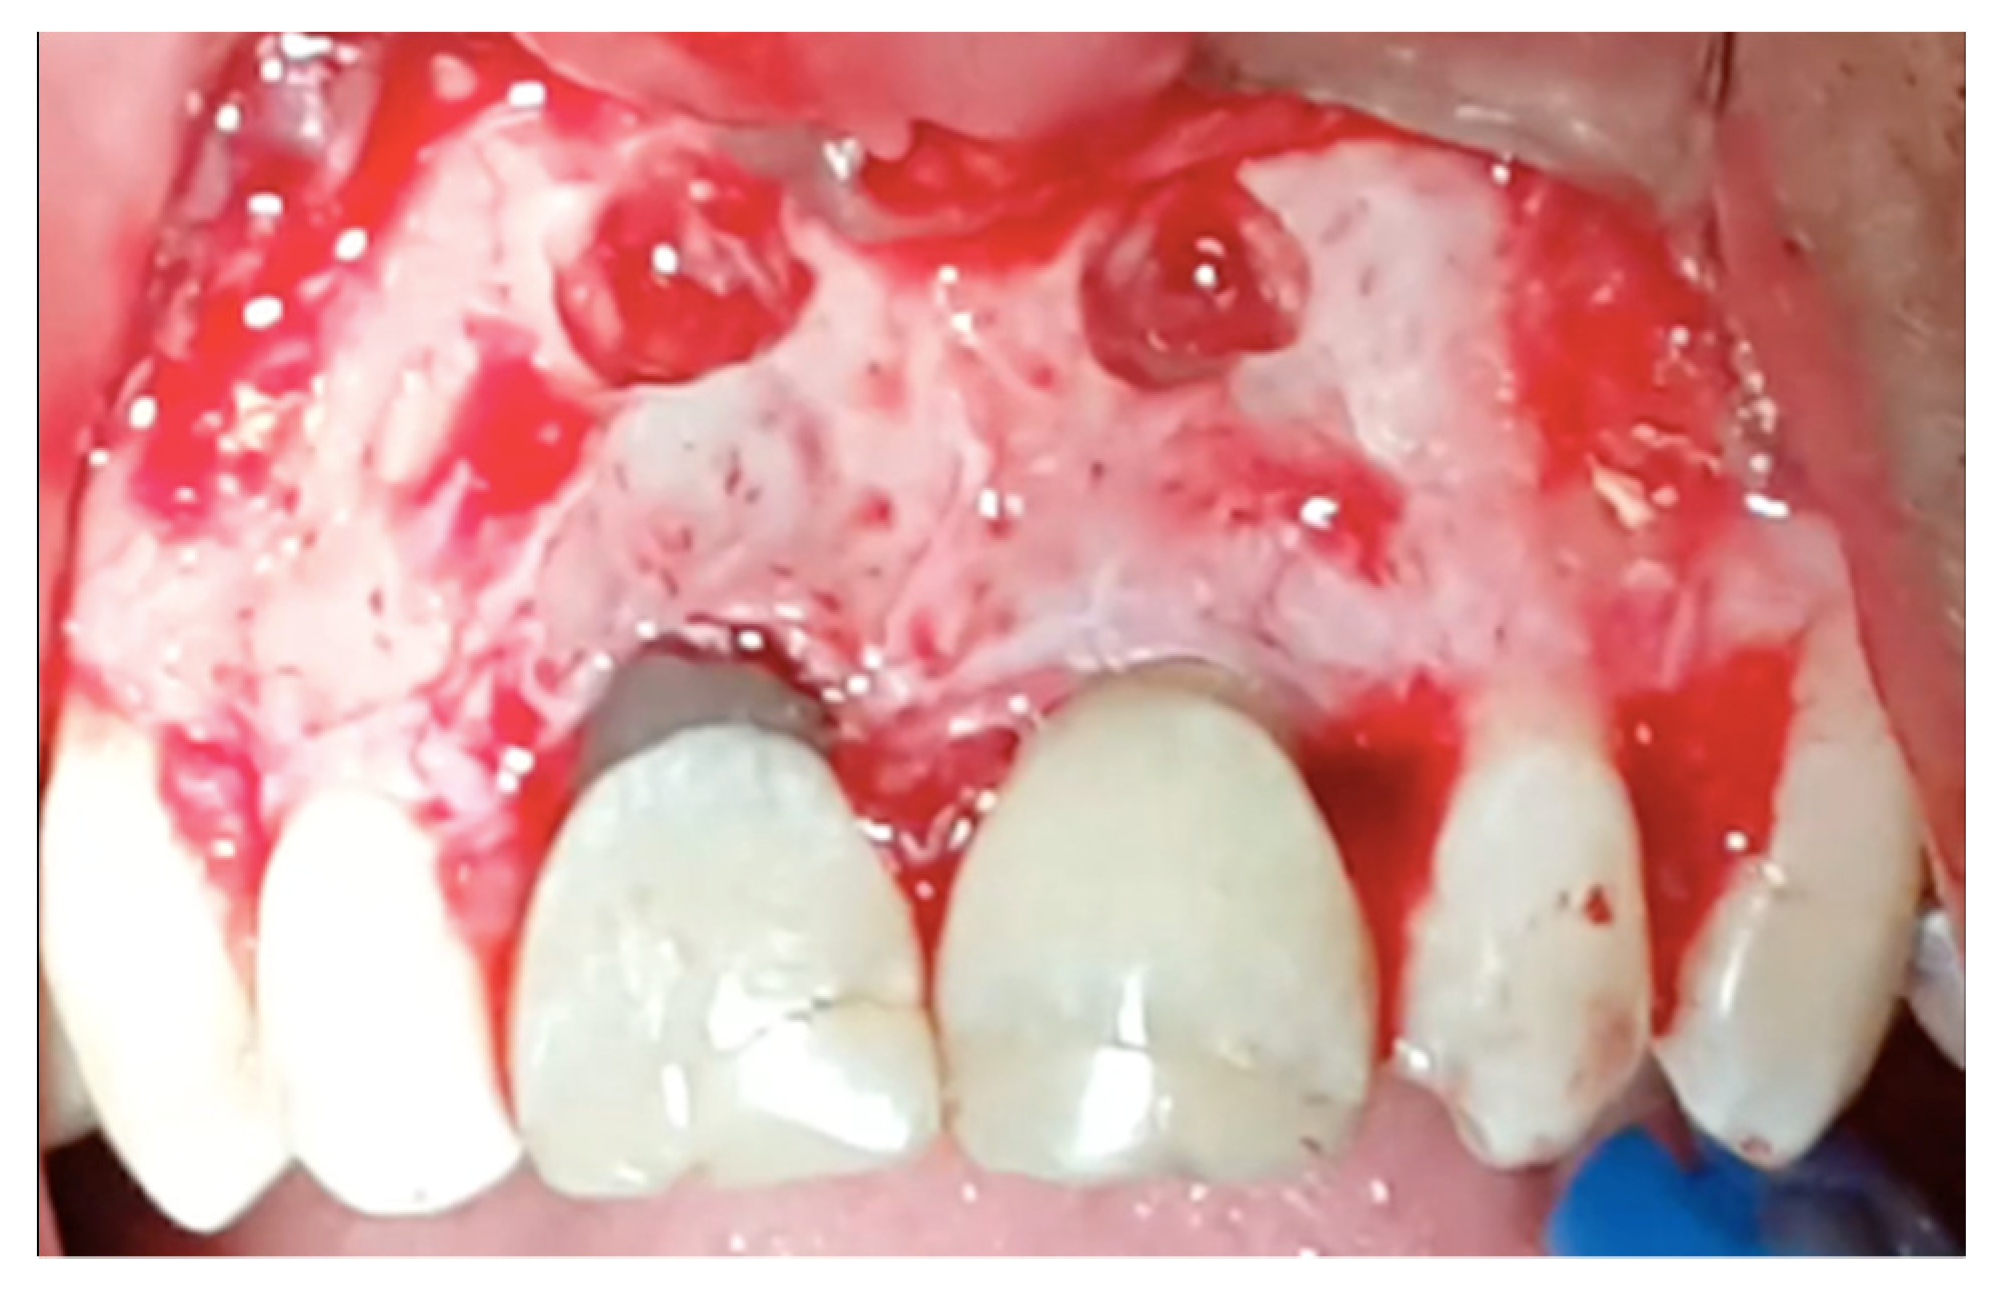

Figure 2.

A full-thickness mucoperiosteal flap was reflected and the window was created around the periapical area of teeth 11 and 21.